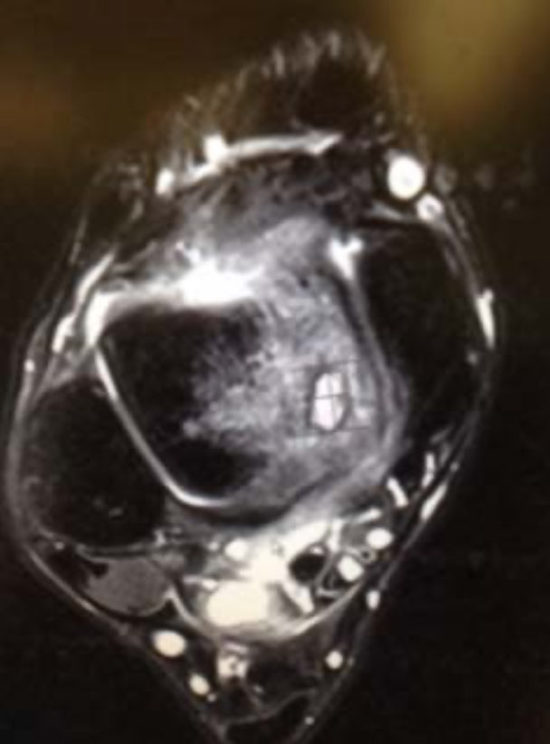

Initial imaging should include anteroposterior (AP), medial oblique (MO), and lateral radiographs of the ankle to evaluate for a defect. It is imperative the treating physician appreciate the mechanism of injury and thoroughly evaluate the radiographs personally for a lesion on the talus. If a more detailed view of the OCD is warranted, an MRI can be obtained. MRI is considered the gold standard in imaging for juvenile OCD of the talus and is found to be highly accurate, with a sensitivity of 92% and specificity of 50%. CT scans may also provide a useful better evaluation of the subchondral bone and could assist with surgical planning.10